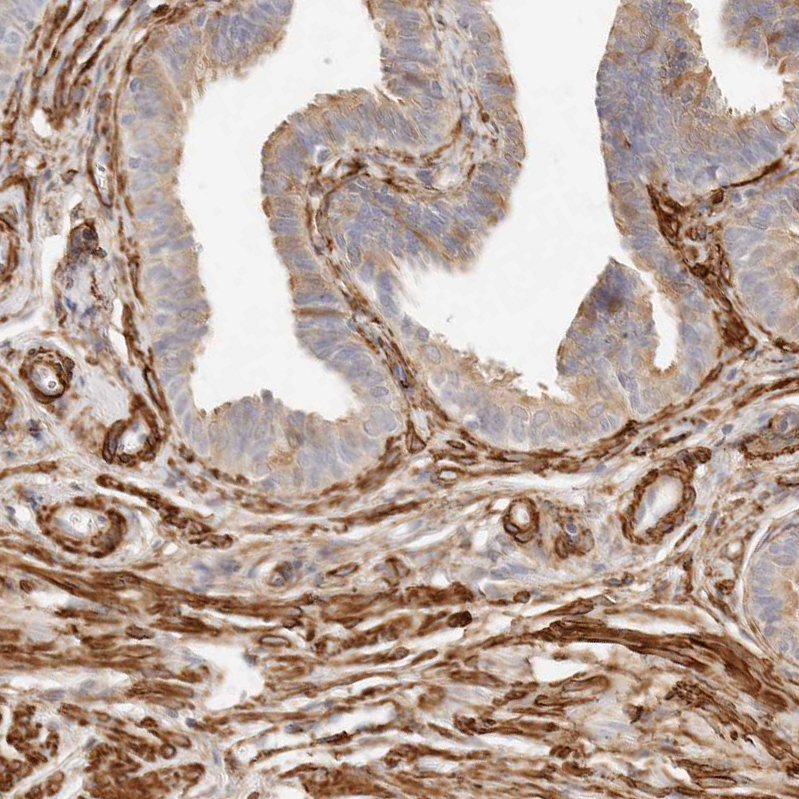

Immunohistochemical staining of human fallopian tube shows strong cytoplasmic positivity in stromal cells.